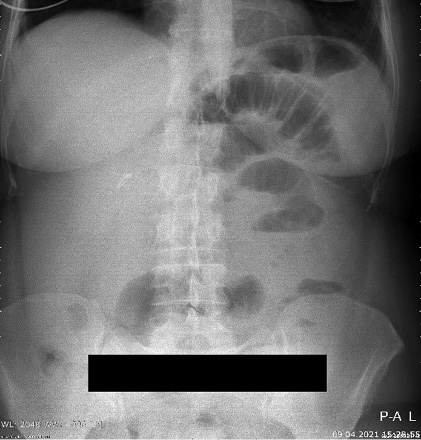

A 46-years-old female patient presented to the emergency department with clinical signs of intestinal obstruction. The patient reported cramp and abdominal pain, and absence of flatus and stool passage one day prior to the exam. She had no previous abdominal surgery nor visible groin herniation on physical examination. The serum analysis showed C-reactive protein value of 5.80 (0.0–5.0 mg/L) and serum Iron level of 5.80 (6.6–28.3 μmol/L). Plain abdominal upright X-ray image confirmed the suspicion for intestinal obstruction (Figure 1).

Figure 1. Plain abdominal X-ray with small bowel air-liquid levels